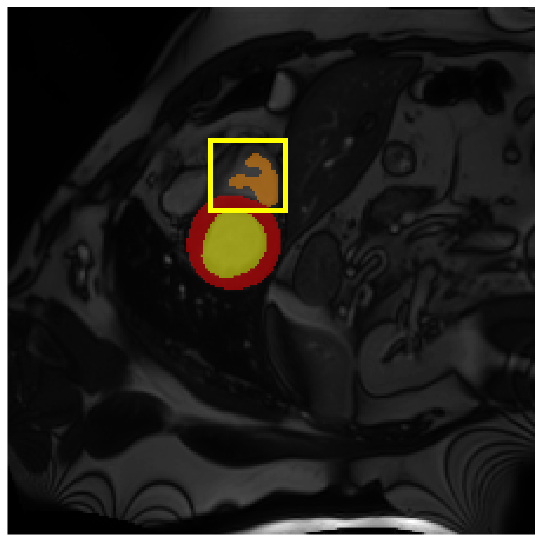

Medical image segmentation plays a critical role in various diagnostic workflows, as it enables accurate delineation of anatomical structures and pathological regions, thereby enhancing disease interpretation, treatment planning, and outcome prediction. Jang et al. [1] has demonstrated that improved segmentation performance can lead directly to reduced diagnostic error rates and increased clinician confidence. Building on the remarkable success of deep learning across diverse domains [2, 3, 4, 5], recent progress in medical image segmentation has been primarily driven by deep learning. Since the introduction of U-Net [6], segmentation methods have rapidly evolved, with convolutional neural networks (CNN)-based models [7, 8, 9] and Transformer-based models [10, 11, 12] showing superior performance in computed tomography (CT) and magnetic resonance imaging (MRI) segmentation. However, various challenges such as blurriness, noise, and low contrast often hinder the accurate diagnosis of diseases. Applying various image enhancement techniques to generate an enhanced image from the input can alleviate this problem, as existing methods have demonstrated improved segmentation accuracy [13, 14, 15]. Nevertheless, input images may unintentionally lose crucial information contained in the original image during enhancement. As a result, the segmentation model suffers from performance degradation (Fig. 1(a) and (b)). Therefore, we argue that it is crucial to leverage the advantages of both the original and enhanced images through image fusion strategies.

| (a) | (b) | (c) | (d) |

4.3.2 Visual Comparisons

Visualization of our method on the Synapse and ACDC datasets is shown in Fig. 3(a) and Fig. 3(b). For the Synapse dataset illustrated in Fig. 3(a), FCT failed to accurately segment SM and GB, while MERIT achieved precise segmentation of SM but struggled with GB. In contrast, our method achieved accurate segmentation of both SM and GB. Regarding the ACDC dataset shown in Fig. 3(b), while previous methods achieve comparable segmentation of the Myo and LV to the GT, they exhibit noticeable errors on the RV, including invasion into adjacent organs and misrecognition. On the other hand, our method accurately segments across all three structures Myo, LV, and RV, performing as precisely as the GT. We demonstrate the superiority of our method quantitatively and qualitatively.